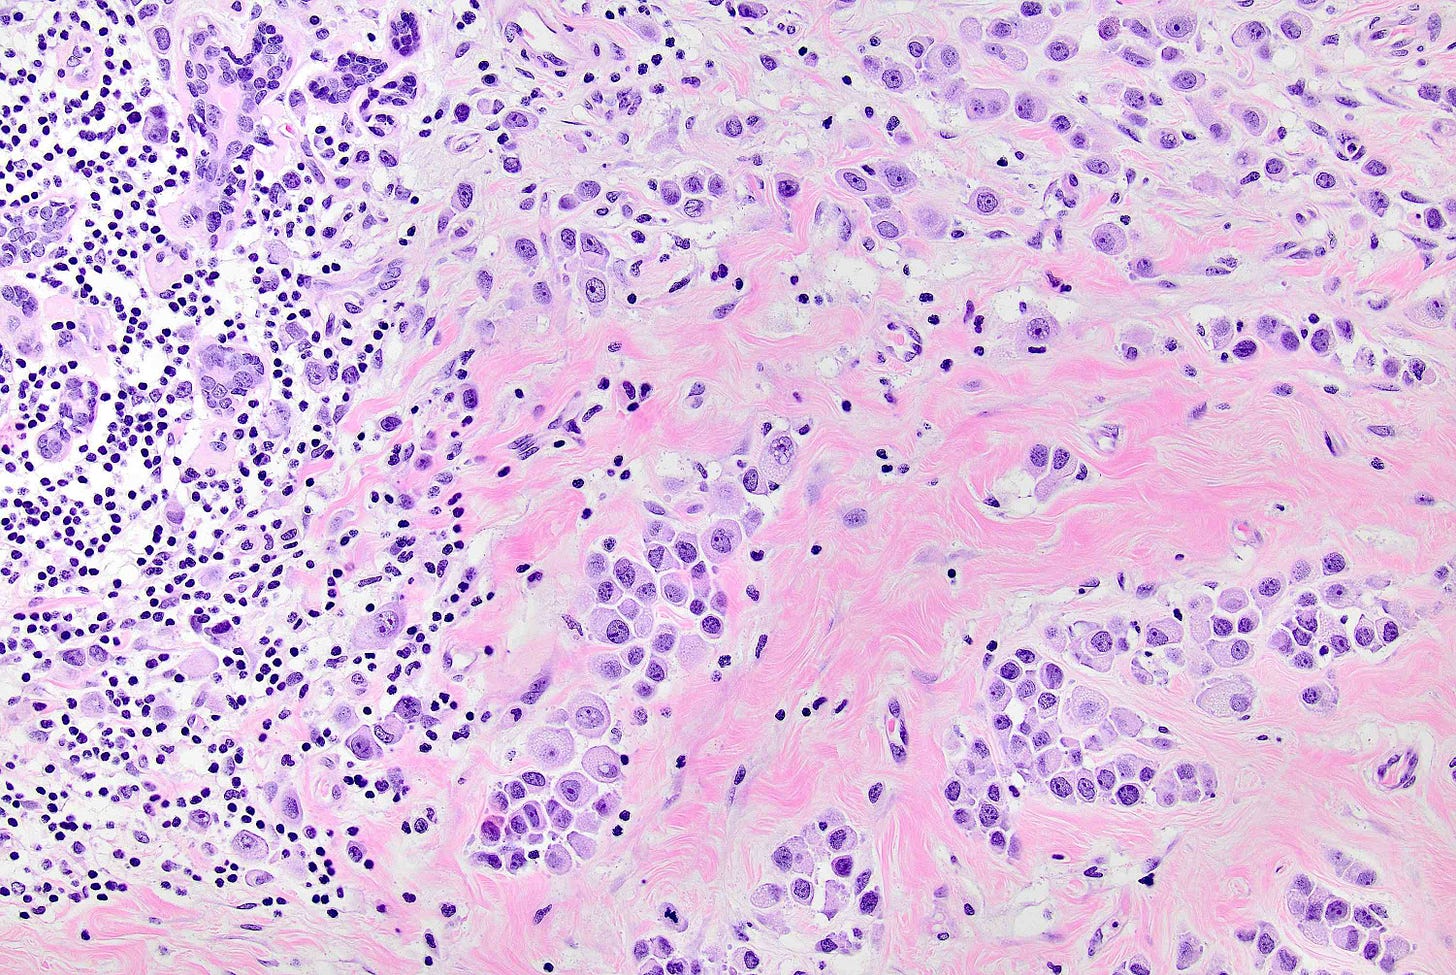

Pleomorphic LCIS is a rare (< 5% of LCIS) nonclassical or variant form of lobular carcinoma in situ composed of a noninvasive, neoplastic proliferation of large dyscohesive cells with marked nuclear pleomorphism. Its nuclei are > 4 times the size of a lymphocyte and its cytologic features more closely resemble high grade DCIS than classic LCIS. It may exhibit comedonecrosis and calcifications. However, other features overlap with classic LCIS: loss or dysfunction of E-cadherin, cellular dyscohesion, lack of cell polarity, intracytoplasmic lumina, signet ring cells and pagetoid spread. Most cases are associated with classic LCIS and ALH.

Pleomorphic LCIS accumulates additional alterations and generally exhibits greater genomic instability than classic LCIS.

Pleomorphic LCIS has features of a high risk precursor lesion of invasive carcinoma. It is associated with a high incidence (49%) of associated invasive carcinoma either on core needle biopsy or excision. Treatment consists of surgical excision but there is no consensus on requiring negative margins, adjuvant treatments or sentinel node biopsy.

Pleomorphic lobular carcinoma in situ - microscopic images